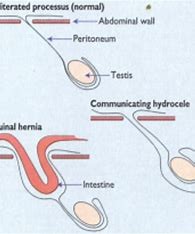

نمای شماتیک هرنی کشاله ران وهیدروسل مرتبط

تقریبأ تمام موارد هرنی کشاله ران / هیدروسل مرتبط در کودکان مادرزادی هستند. در پسربچه ها ابتدا بیضه در داخل شکم است. حوالی ماه هفتم بارداری، بیضه ها با عبور از کانال کشاله ران(inguinal canal) ، به داخل کیسه بیضه مهاجرت میکنند. این کانال به صورت طبیعی کمی پس از تولد بسته میشود. در صورتی که کانال کاملأ بسته نشود، هرنی یا هیدروسل پدید می آید. در دخترها کانال کشاله ران محل عبور رباط نگاهدارنده رحم است. اگر در فتق دختر بیضه دیده شود؛ تست ژنتیک ضروری است.

در هیدروسل طناب بیضه، مجرای ارتباطی در سمت بالا و پایین بسته شده و مایع فقط در بخشی در مجاورت طناب بیضه تجمع می یابد.

هیدروسل شکمی- کیسه بیضه ای ( آبدومینو اسکروتال )، شکل نادری از هیدروسل است که با حفره شکمی ارتباط ندارد. این نوع هیدروسل، دو کیسه دمبل شکل است که یک جزء آن در کیسه بیضه و جزء دیگر در حفره شکم واقع شده است. این دو کیسه توسط مجرایی با یکدیگر ارتباط دارند و این نوع هیدروسل، قوام سفت داشته و بر خلاف هیدروسل مرتبط در طول شبانه روز تغییر نمیکند. هیدروسل شکمی- کیسه بیضه ای ( آبدومینو اسکروتال[abdominoscrotal hydrocele] ) توسط سونوگرافی تأیید میشود. در صورت تغییر شکل دوکی بیضه در سونوگرافی و کاهش جریان خون بیضه در سونوگرافی داپلر رنگی(color Doppler)، توصیه به جراحی در اسرع وقت میشود.